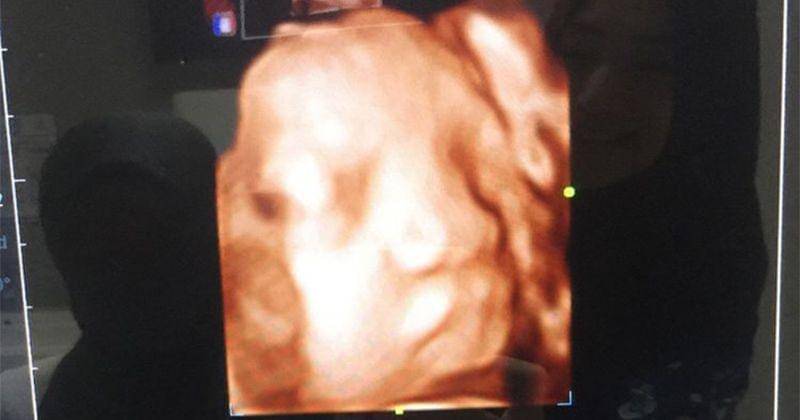

1. Mencoba USG 4D

Indri Giana salah satu ibu hamil yang mencoba melihat si Kecil di dalam kandungan menggunakan USG 4 dimensi. Istri Ustadz Riza Muhammad melakukan USG 4 dimensi ini saat masa kehamilan di minggu ke-32.

"Baru pertama kali nyobain USG 4D di RS Brawijaya Depok. Baru ini dapat wajahnya, meskipun masih samar-samar anak ini pemalu banget. Berapa kali mau ditengok ke tutup plasenta," tulis Indri Giana melalui Instagram saat masa-masa kehamilannya.

Seiring kemajuan teknologi, banyak ibu hamil yang melakukan USG dengan 4 dimensi. Sebenarnya USG 4 dimensi memberikan gambar yang terlihat lebih detail dan akurat.

Selain memberikan sebuah gambar detail sesuai keinginan ibu hamil. USG 4 dimensi juga dapat membantu dokter kandungan dalam mendeteksi kelainan yang tinggi.